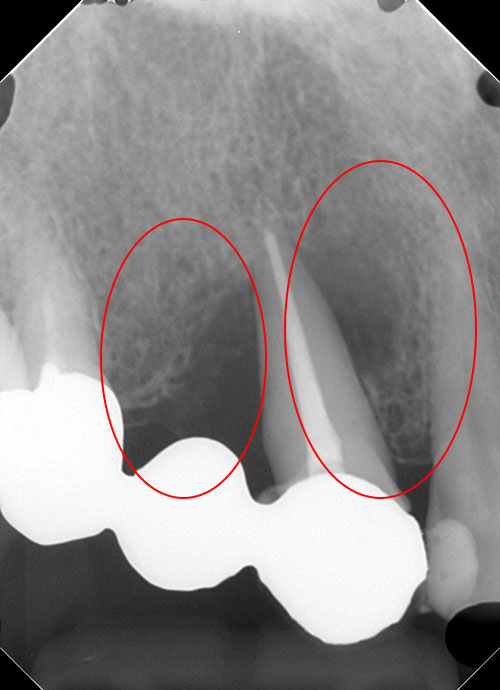

リグロス(歯周組織再生療法)の症例

年齢/性別が表示されたボタンを押すと、下部にスクロールして症例の画像と詳細をご覧になれます。